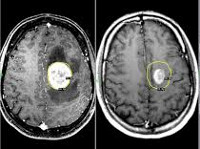

C79.3 Вторичное злокачественное новообразование головного мозга и мозговых оболочек